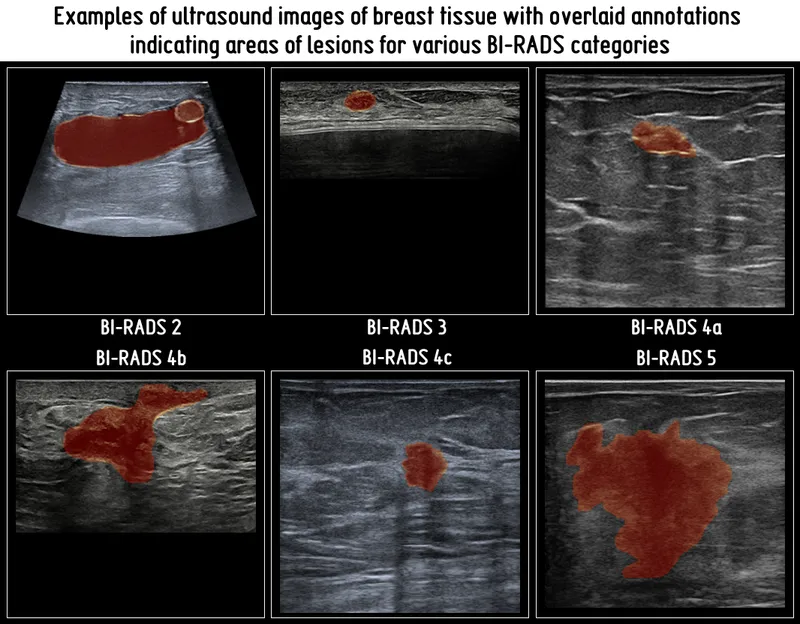

BI‑RADS Blueprint - Code Red or Green?

- BI-RADS (Breast Imaging Reporting and Data System) provides a universal language for breast imaging, standardizing mammography, ultrasound, and MRI report conclusions and recommendations.

- Its 7 assessment categories (0-6) are pivotal, directly dictating patient management: from additional evaluation or routine screening to biopsy and confirmed malignancy treatment.

⭐ BI-RADS 3 (Probably Benign) lesions have a <2% risk of malignancy; typically managed with short-term (e.g., 6-month) follow-up, avoiding unnecessary immediate biopsies.

- BI-RADS standardizes reporting, guiding management from benign (BI-RADS 2) to malignant (BI-RADS 5).